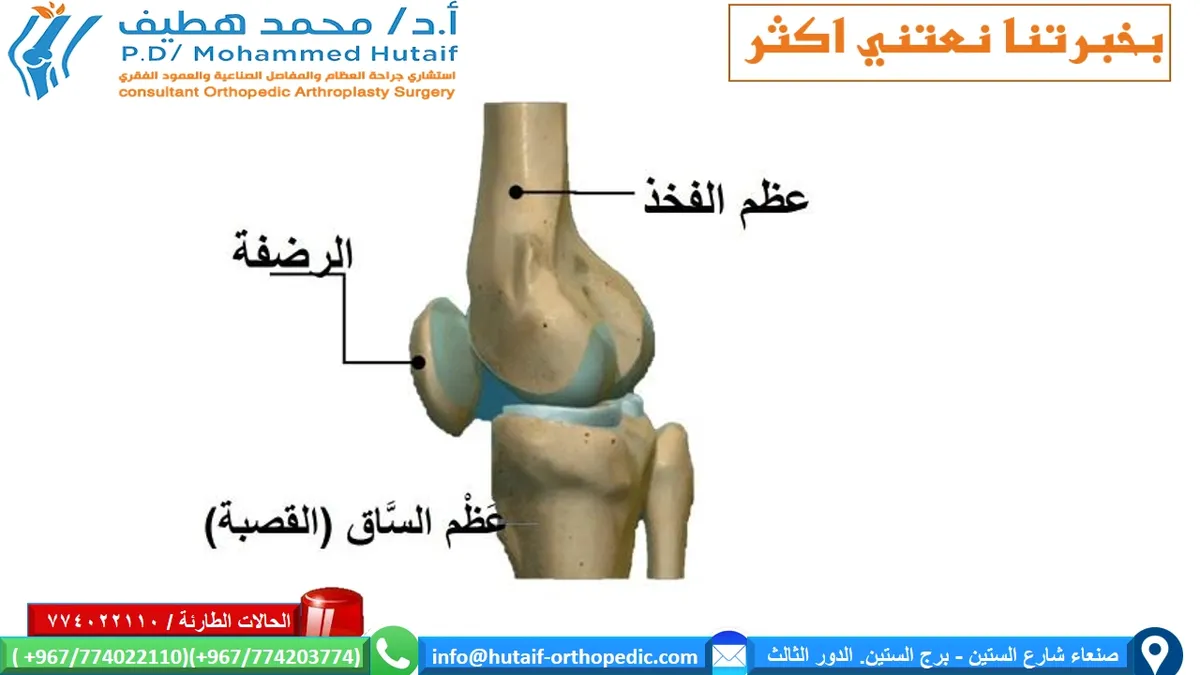

التشريح الأساسي لمفصل الركبة

مفصل الركبة هو أحد أكبر وأكثر المفاصل تعقيدًا في جسم الإنسان، وهو ضروري للمشي والجري والانحناء والعديد من الحركات اليومية. يتكون المفصل بشكل أساسي من التقاء ثلاثة عظام رئيسية:

*

عظم الفخذ (Femur):

العظم العلوي الطويل الذي يمتد من الورك إلى الركبة.

*

عظم الساق (Tibia):

العظم الأكبر في الجزء السفلي من الساق، والذي يمتد من الركبة إلى الكاحل.

*

الرضفة (Patella):

العظم الصغير المسطح المعروف باسم "صابونة الركبة"، والذي يقع أمام المفصل لحمايته.

تُغطى نهايات هذه العظام بغضروف أملس ومرن يُعرف باسم "الغضروف المفصلي" (Articular Cartilage)، والذي يسمح للعظام بالانزلاق بسلاسة فوق بعضها البعض دون احتكاك، مما يسهل الحركة ويقلل من الصدمات. يحيط بالمفصل كبسولة مفصلية تحتوي على سائل زلالي (Synovial Fluid) يعمل كمادة تشحيم. تدعم الأربطة القوية، مثل الأربطة الصليبية والأربطة الجانبية، المفصل وتوفر له الاستقرار.